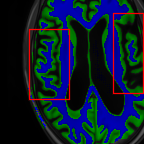

Sparsity LI 2D CNN 3D CNN Ours GT

4 Refer to caption (a) 0.6787/0.7972 Refer to caption (b) 0.8143/0.8776 Refer to caption (c) 0.8190/0.8714 Refer to caption (d) 0.8664/0.9085 Refer to caption (e) GM/WM

Refer to caption (f) 0.6808/0.7161 Refer to caption (g) 0.8103/0.8631 Refer to caption (h) 0.7950/0.8606 Refer to caption (i) 0.8598/0.9115 Refer to caption (j) GM/WM

Figure 6: Visual comparison of gray matter (Green)/white matter (Blue) segmentation over different methods, with respective DICE scores listed under the images.

In Fig. 6, we demonstrate the advantage of the proposed method in brain matter segmentation. It is clear that although 2D and 3D CNN generates visually plausible interpolation as presented in Fig. 5, the brain matters are easily misclassified due to incorrect anatomical structures and blurred details.